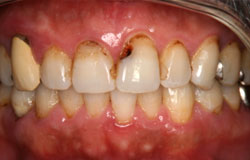

深い虫歯で歯の神経にまで達している。また歯周病で歯が揺れ、根っこがむき出しになりしみて仕方がない。そんな場合は神経を取らなくてはいけないことがあります。

しかし、歯を残すためにきちんと根管治療をすることで歯の寿命は延びます。

神経を取ったあと、神経が入っていた根管を清掃して、根の先にまで薬を入れます。かぶせ物などになる土台になる治療なので、歯を残すためには最も大切な処置です。